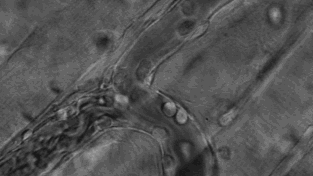

免疫细胞可穿过血管壁奔赴“战场”,向炎症和创伤组织进军、围剿。

中性粒细胞可以吞噬和消化有害病原体,图中为中性粒细胞追击金黄色葡萄球菌的过程。